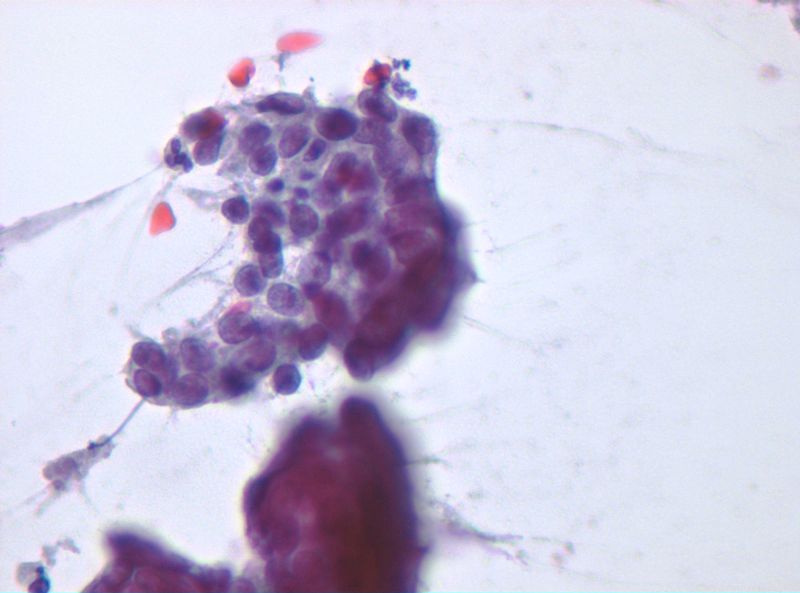

Althaia, xarxa assistencial universitària de Manresa

Dona de 50 anys, en cribatje de mama des dels 40; assimtomàtica. En una de les mamografies es troben calcificacions en QIE de mama esquerra de nova aparció.

En els controls succesius aparició de tumoració en QIE mama esquerra amb traducció radiològica de quist complicat de 13mm.

Es realitza PAAF: el diagnòstic es de abundant cel·lularitat inflamatoria, negatiu per cèl·lules malignes. Material citològic compatible amb quist.